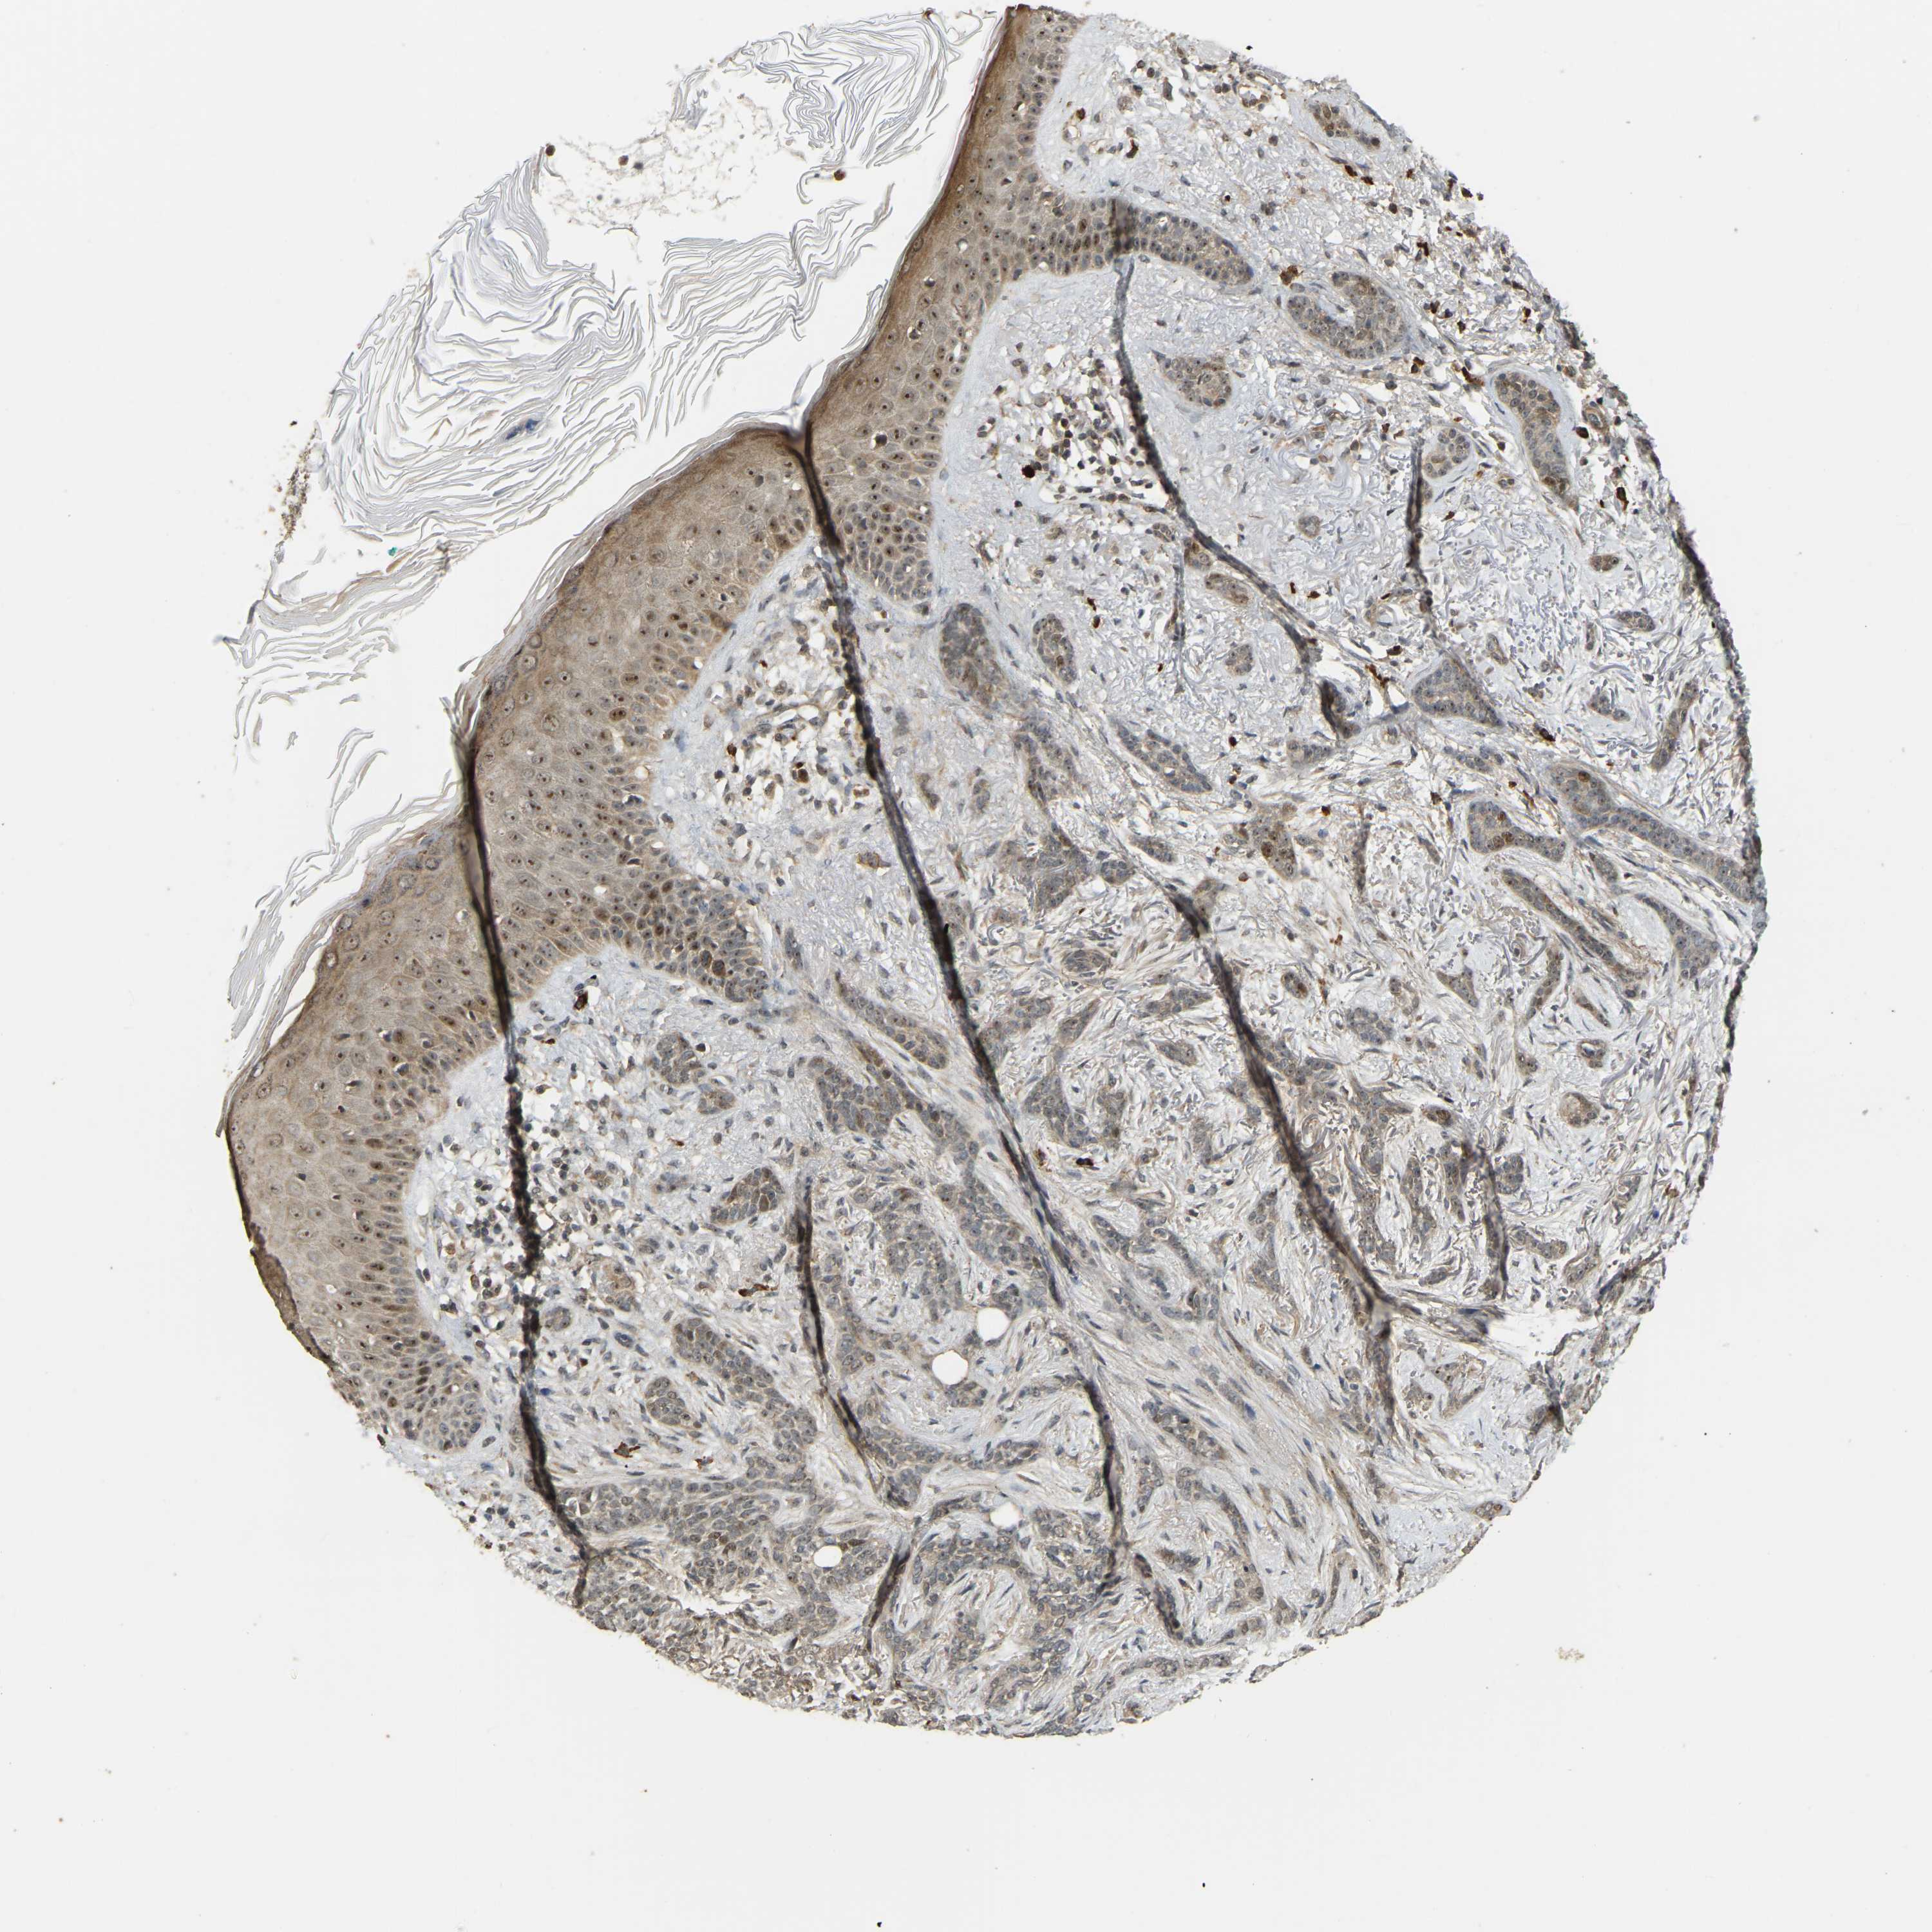

SKIN CANCER - Protein expressioni

A mouse-over function shows sample information and annotation data. Click on an image to view it in a full screen mode. Samples can be filtered based on level of antibody staining by selecting one or several of the following categories: high, medium, low and not detected. The assay and annotation is described here.

Antibody stainingi

Antibody staining in the annotated cell types in the current human tissue is reported as not detected, low, medium, or high, based on conventional immunohistochemistry profiling in selected tissues. This score is based on the combination of the staining intensity and fraction of stained cells.

Each image is clickable and will lead to virtual microscopy that enables deeper exploration of all samples and also displays staining intensity scores, fraction scores and subcellular localization as well as patient and tissue information for each sample.

Antibody HPA023378

Basal cell carcinoma